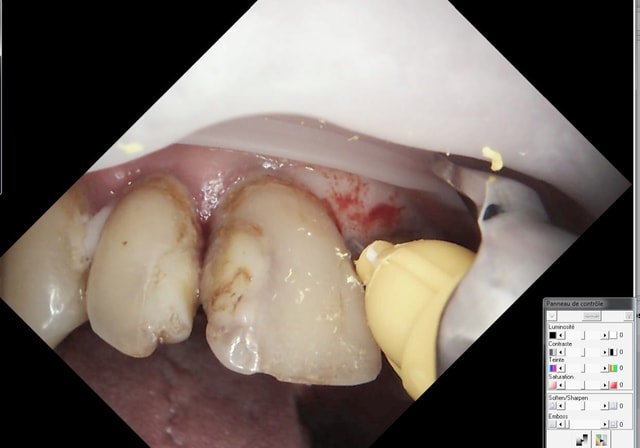

je suis decu que tu n'es pas tenter une couronne sur la 25 chicot, je t'ai deja vu faire des ccm avec des truc bien plus profonds

Sinon c'est bizarre ta methode de piquer au palais. Pourquoi tu fais pas d'intraosseuse classique (voie vestibulaire à 45 degré sur la papille)

20/10/2015 à 21h57

Je fais aussi, mais cet endroit est plus direct.